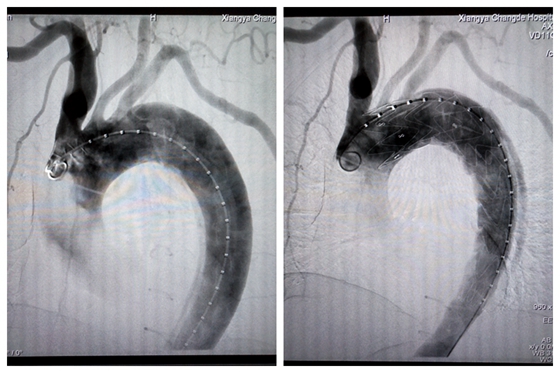

手术前后对比图

主动脉夹层覆膜支架腔内隔绝术是指经股动脉导入覆膜支架,以覆膜支架固定于主动脉壁上,将破口与血液隔绝,使破口免受血流直接冲击以达到目的的介入治疗方法。现在湘雅常德医院心胸外科黄日茂教授的带领下不到一小时就完成了该类手术的首秀,同时也展示了该手术的优势:手术创伤小(传统手术需要正中开胸或开腹),手术时间短,手术疼痛轻,术中术后无明显出血,术后住院时间短(约4天)等。开展该手术不仅增加床位利用率,还最大限度的减轻了患者的痛苦。